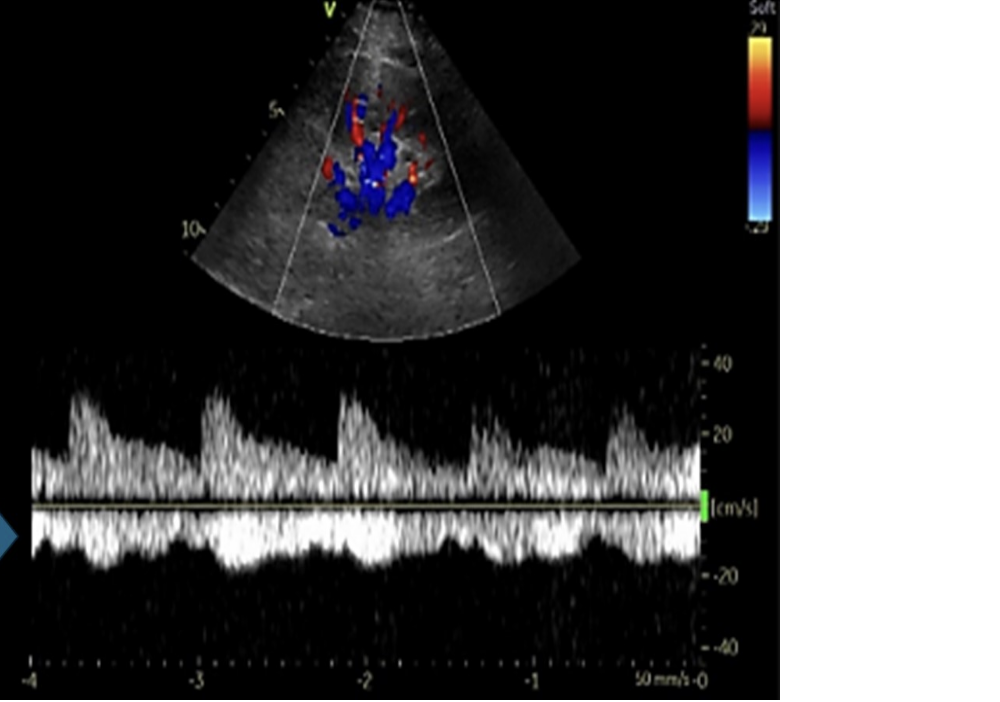

![<p>which describes a normal renal artery waveform</p><p>.</p><p>a) low resistance w/increased diastolic flow</p><p>b) increased diastolic flow reversal</p><p>c) biphasic w/mild diastolic flow reversal</p><p>d) pulsus alternans [methodical variation in peak vel on every other beat]</p>](https://knowt-user-attachments.s3.amazonaws.com/8c8e8b11-eaa0-4474-8147-a50abca9736d.png)

which describes a normal renal artery waveform

a) low resistance w/increased diastolic flow

b) increased diastolic flow reversal

c) biphasic w/mild diastolic flow reversal

d) pulsus alternans [methodical variation in peak vel on every other beat]

a. low resistance w/increased diastolic flow